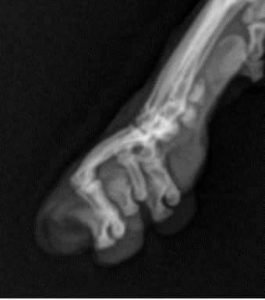

Declawed Xray1